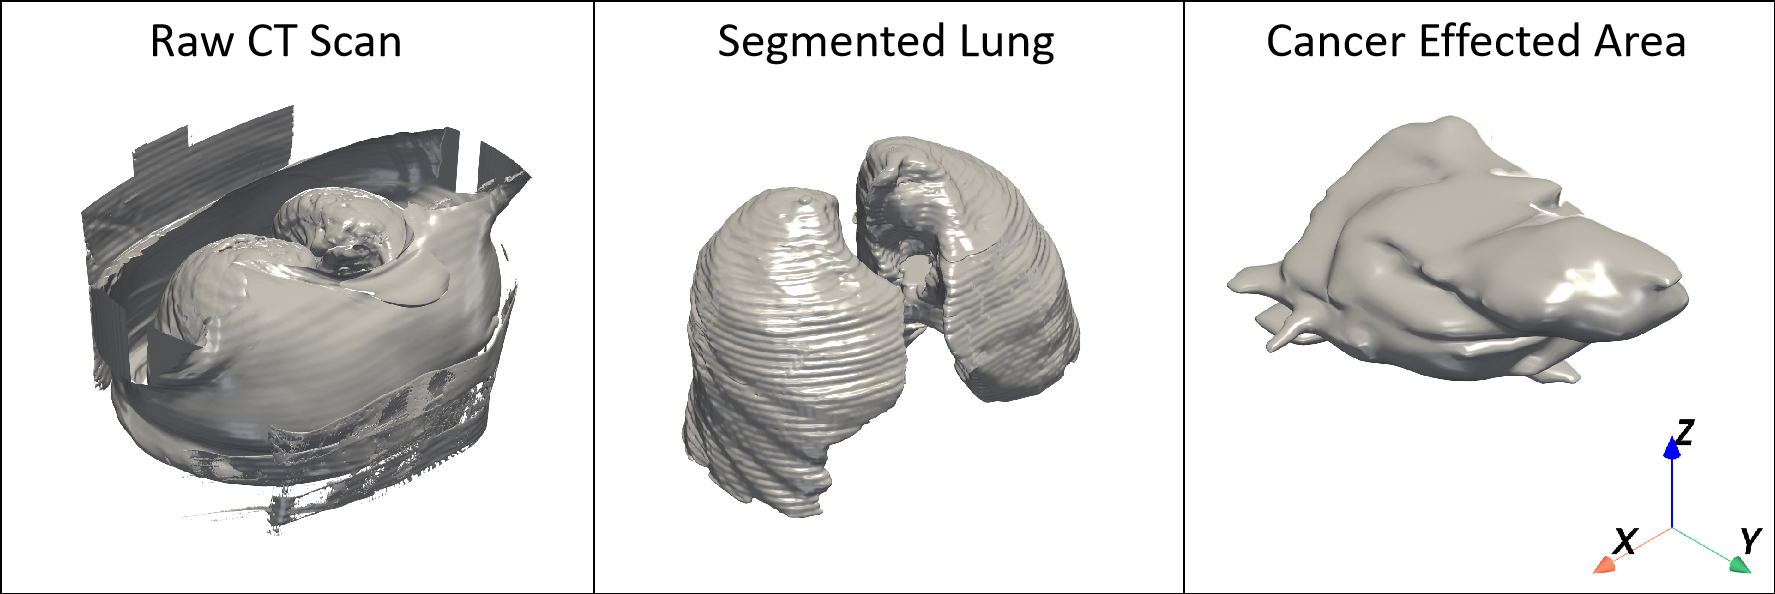

Raw CT scan (left), extracted lung region (middle), and cancer-affected regions (right).